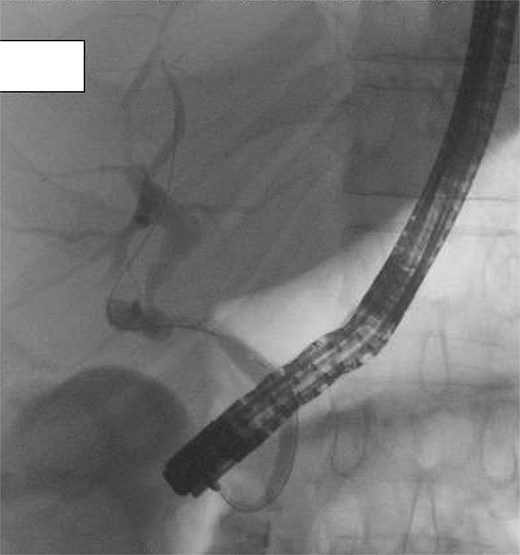

A four-port laparoscopic cholecystectomy was performed on Day 3 after symptom resolution. After obtaining the critical view of safety, an incision of the infundibulo-cystic junction was made and intra-operative cholangiogram performed, however biliary anatomy was difficult to interpret (Fig. 1A). The cystic ductotomy was closed and a higher incision on the gallbladder infundibulum made to better delineate the anatomy with a high cholangiogram. Again, biliary anatomy could not be easily interpreted, prompting conversion to open. A third cholangiogram with the gallbladder compressed to facilitate preferential filling of the cystic duct (CD) and common hepatic duct (CHD) was performed, revealing the CHD was draining directly into the gallbladder infundibulum from the liver and that the entire biliary drainage from the liver and gallbladder to ampulla of Vater was via the cystic duct, identified via its spiral valves (Fig. 1B). There was a stricture just proximal to where the CHD drained into the infundibulum, but otherwise the biliary tree was intact with nil evidence of redundancy or stricturing of the CBD (Fig. 2A). There were no large stones, inflammatory erosion, or evidence of cholecystobiliary fistulization to suggest Mirizzi syndrome. After intra-operative consultation with two other consultant hepatobiliary surgeons, a reconstituting subtotal cholecystectomy was performed, ensuring the infundibulum, with the draining CHD and cystic ducts, was preserved (Fig. 2B).

(A) Initial intra-operative cholangiogram, difficult to interpret biliary anatomy. (B) Intra-operative cholangiogram once converted to open, revealed the common hepatic duct was draining directly into the gallbladder infundibulum from the liver, and that the entire biliary drainage from the gallbladder to the ampulla of Vater was via the cystic duct.